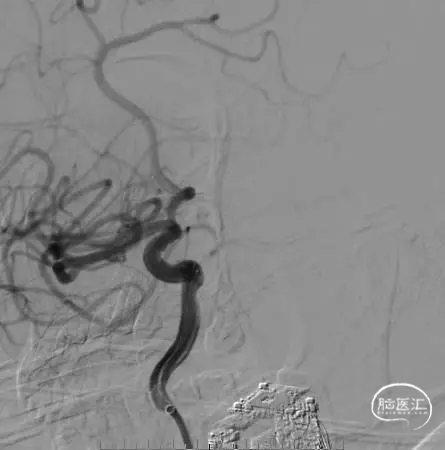

术后即刻影像

本例病例为带有子囊的后交通动脉瘤伴胚胎型大脑后动脉,为了降低术中破裂风险,提高安全性和栓塞效果,采用双微导管技术,同时弹簧圈的均匀分布,柔顺性和钻缝能力同样重要,Jasper®SS弹簧圈展现出了非常优秀的柔顺性和较强的钻空能力,在整个填塞过程中没有出现踢管现象,增加了动脉瘤栓塞的致密性,降低了术者操作的难度。